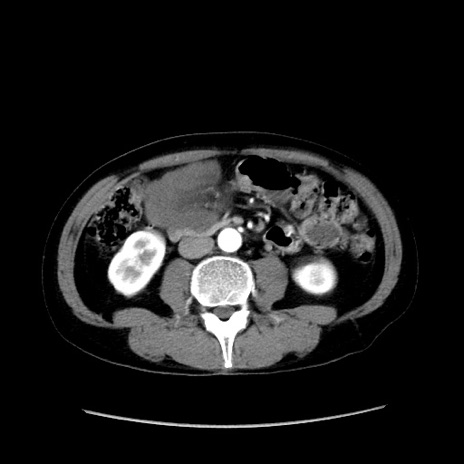

症例37(横断像)

【症例】40歳代 男性

【主訴】腹痛

【現病歴】4時間ほど前に電車に乗車中に臍部上より腹痛出現。徐々に増悪し起立困難となり、救急外来受診。生ものは数日食べていない。今朝お雑煮を食べた。

【身体所見】BT 36.8℃、BP 117/84mmHg、HR 91/min、SpO2 97%、苦悶様、腹部:臍上部広範囲圧痛あり、反跳痛±

【データ】WBC 8100、CRP 0.03